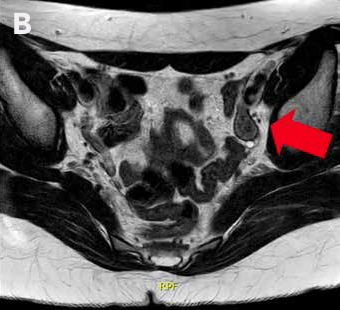

La RM de abdomen y pelvis (Figura 1) demuestra agenesia uterina y ausencia de gran parte de cavidad vaginal, reconociendo 2 nódulos de aspecto solido homogéneos en excavación pélvica (posición anexial) con señal sugerente de testículos, con diámetro mayor de 31 mm a derecha y de 21 mm a izquierda.